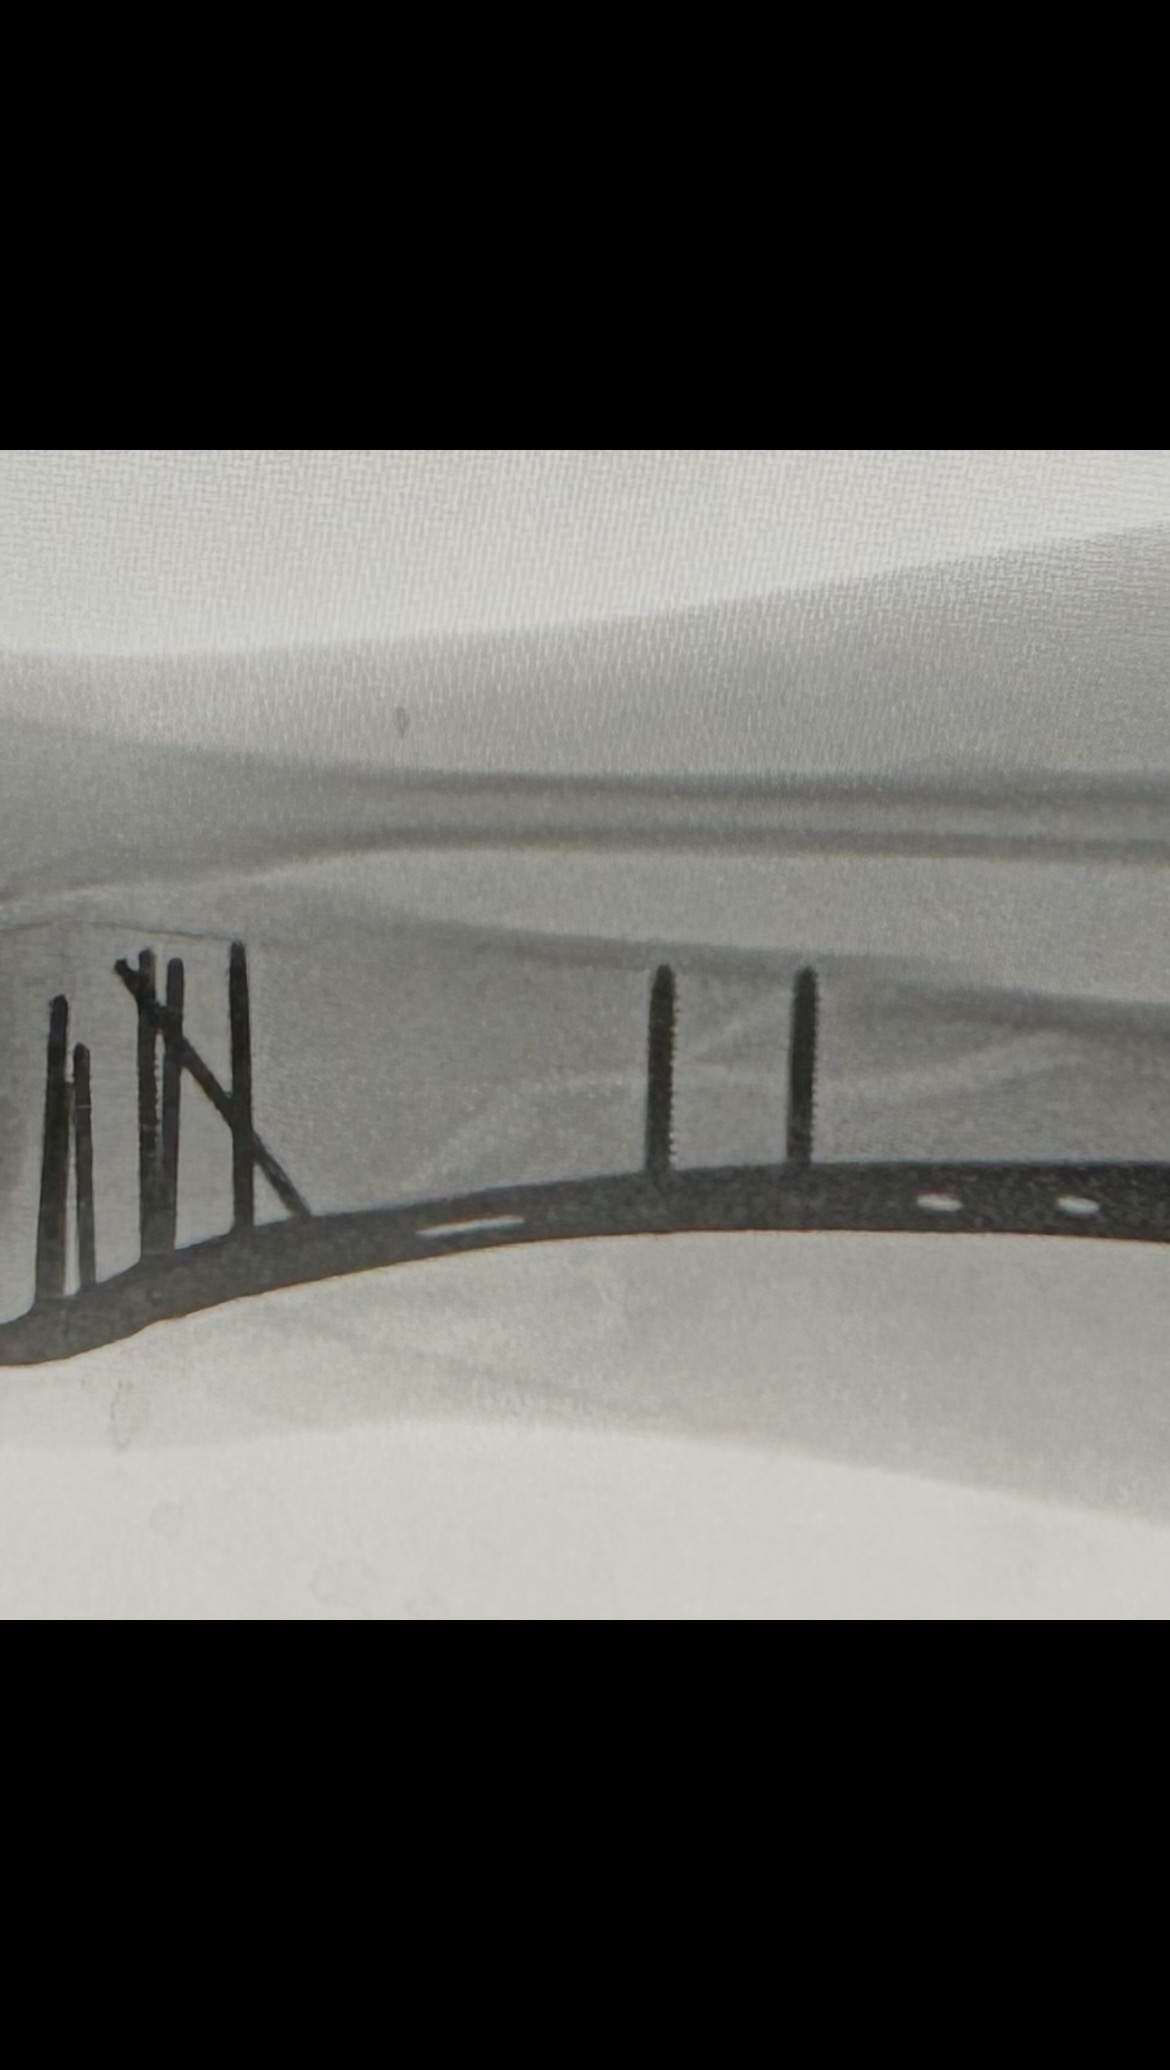

Hello my name is Rachel and I’m usually a pretty active and healthy girl. I was taken to the Murray Hospital February 15th and discharged on the 24th due to severe pancreatitis and pneumonia. I was home only a couple days and still felt very weak and tired. I attempted to go into my bathroom and somehow lost my footing and my whole body landed on my right leg and broke my right tibia and fibula (8.0 cm severely comminuted fracture of the proximal fibular shaft and 10.2 cm spiral fracture distal tibial shaft). 2 very bad fractures . It was the worst pain I’ve ever experienced! It took me 30 mins to crawl about 30 feet to my bed where my phone was to call 911 for help. The paramedics wouldn’t let me look at my leg and kept telling me to try to just lay down and relax, which was extremely hard to do. I was told my leg looked crooked and my foot was turned all the way to the side. With the help of the fire department, I was able to make it down my steps and to the ER. I had 2 doctors come in while in the ER and reset it the best they could until I could have surgery. Was supposed to be the next day but a special plate and screws had to be sent to the hospital so Sunday morning at 8am, an hour long surgery took almost 3. I now have a 9 inch place and 13 screws in my leg on one of the fractures. Depending on how the other fracture looks when I see my Ortho for follow up, I may need another surgery to put a plate on it as well. I am non weight bearing for 6-8 weeks and won’t be able to drive for no earlier than 6 months. Full recovery is a year or more. Since I am not currently working, I have applied and talked to many people about getting some sort of disability to help me keep my apartment but not getting a lot of good answers so far. I have even had my doctors send in letters stating my condition and how severe it is but it’s not getting anywhere. If anyone could find it in their heart to help me stay above water, I would greatly appreciate it!! Even a couple dollars goes a long way! All money will go to medical expenses including physical therapy, doctor appointments, medicine and the rental of medical equipment I need to get around. I didn’t want to have to make this but I’m in a rough place right now and could really use the help. Any help is appreciated. Thank you and God Bless!